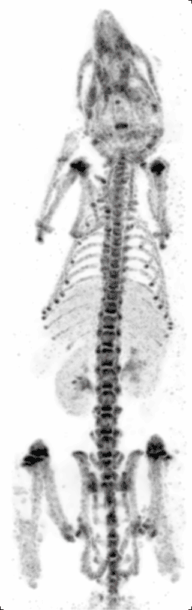

High resolution 99mTc-MDP mouse SPECT scan: animated image of rotating maximum intensity projections.

Principle: Similar to PET, single photon emission computed tomography (SPECT) also images living systems through γ-rays emitted from within the subject. Unlike PET, the radioisotopes used in SPECT (such as technetium-99m) emit γ-rays directly,[8] instead of from annihilation events of a positron and electron. These rays are then captured by a γ-camera rotated around the subject and subsequently rendered into images.